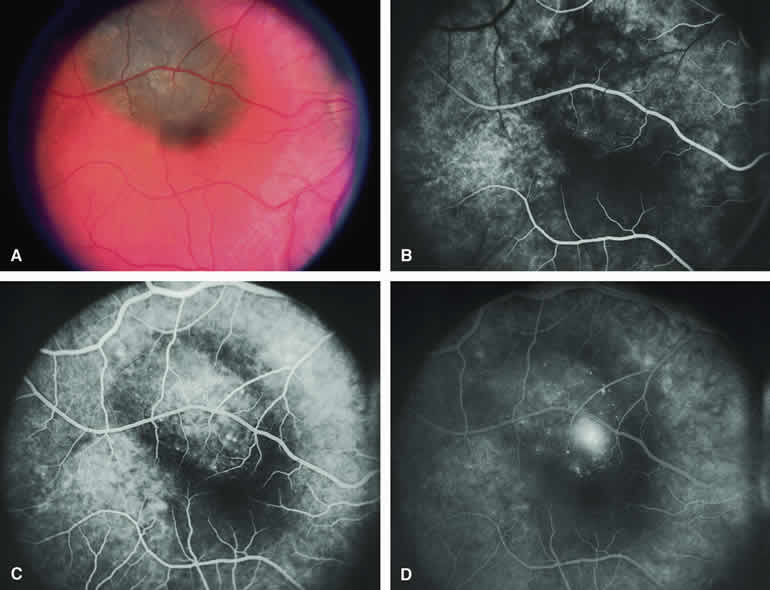

Choroidal Nevus Versus Melanoma with Overlying Serous Subretinal Fluid

A blister of serous subretinal fluid sometimes develops over and around a presumed choroidal nevus (Fig. 7A), especially if the lesion is located in the macula.11 If one performs a fluorescein angiogram on a small melanocytic choroidal lesion (nevus versus melanoma) that has shallow overlying serous subretinal fluid (see Fig. 7B, C, and D), one or more hyperfluorescent leak sites may show up slowly at the RPE level as the study progresses. In some cases, fluorescein will clearly leak from those foci into the overlying serous subretinal fluid. ICG angiography does not show hyperfluorescent leak sites at the RPE level as well as fluorescein angiography does.